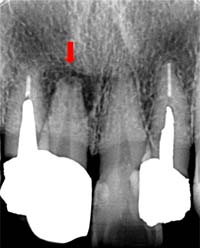

この複雑さは、レントゲンの2D画像だけでは把握できず、肉眼での治療はまさに「懐中電灯なしで洞窟を探検するようなもの」。根管治療が失敗しやすい理由は、見えないものを手探りで治す構造的限界にあります。

当院での治療例です。ご来院された(初診時)治療前の状態と根充後(治療後)の状態をレントゲンとCTで確認すると次のようになります。

しっかりと根充されていることがCTにより確認すことができます。